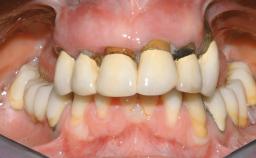

Immediate Loading of Eight Implants in the Maxilla and Six Implants in the Mandible and Final Restoration with Three-Unit and Four-Unit FDPs

Extensive scientific evidence has confirmed that immediately loaded implants with fixed full-arch provisional restorations can osseointegrate with success rates similar to conventionally or delayed loaded implants. A number of immediate-provisionalization techniques for edentulous jaws have been described. Some protocols differ when it comes to prefabricated provisional templates versus complete denture conversion; intrasurgical impressions versus direct relining; and cemented versus screw-retained provisional restorations. In this context, complete-denture conversion has been proposed for either intrasurgical impressions or direct relining. Another possibility is the utilization of a prefabricated provisional to be adapted either in the mouth (by direct relining) or in the laboratory (on a working model obtained from an intrasurgical impression).

Defining Characteristics Fully edentulous upper jaw to be rehabilitated with an implant-borne fixed dental prosthesis

Loading Protocol Immediate